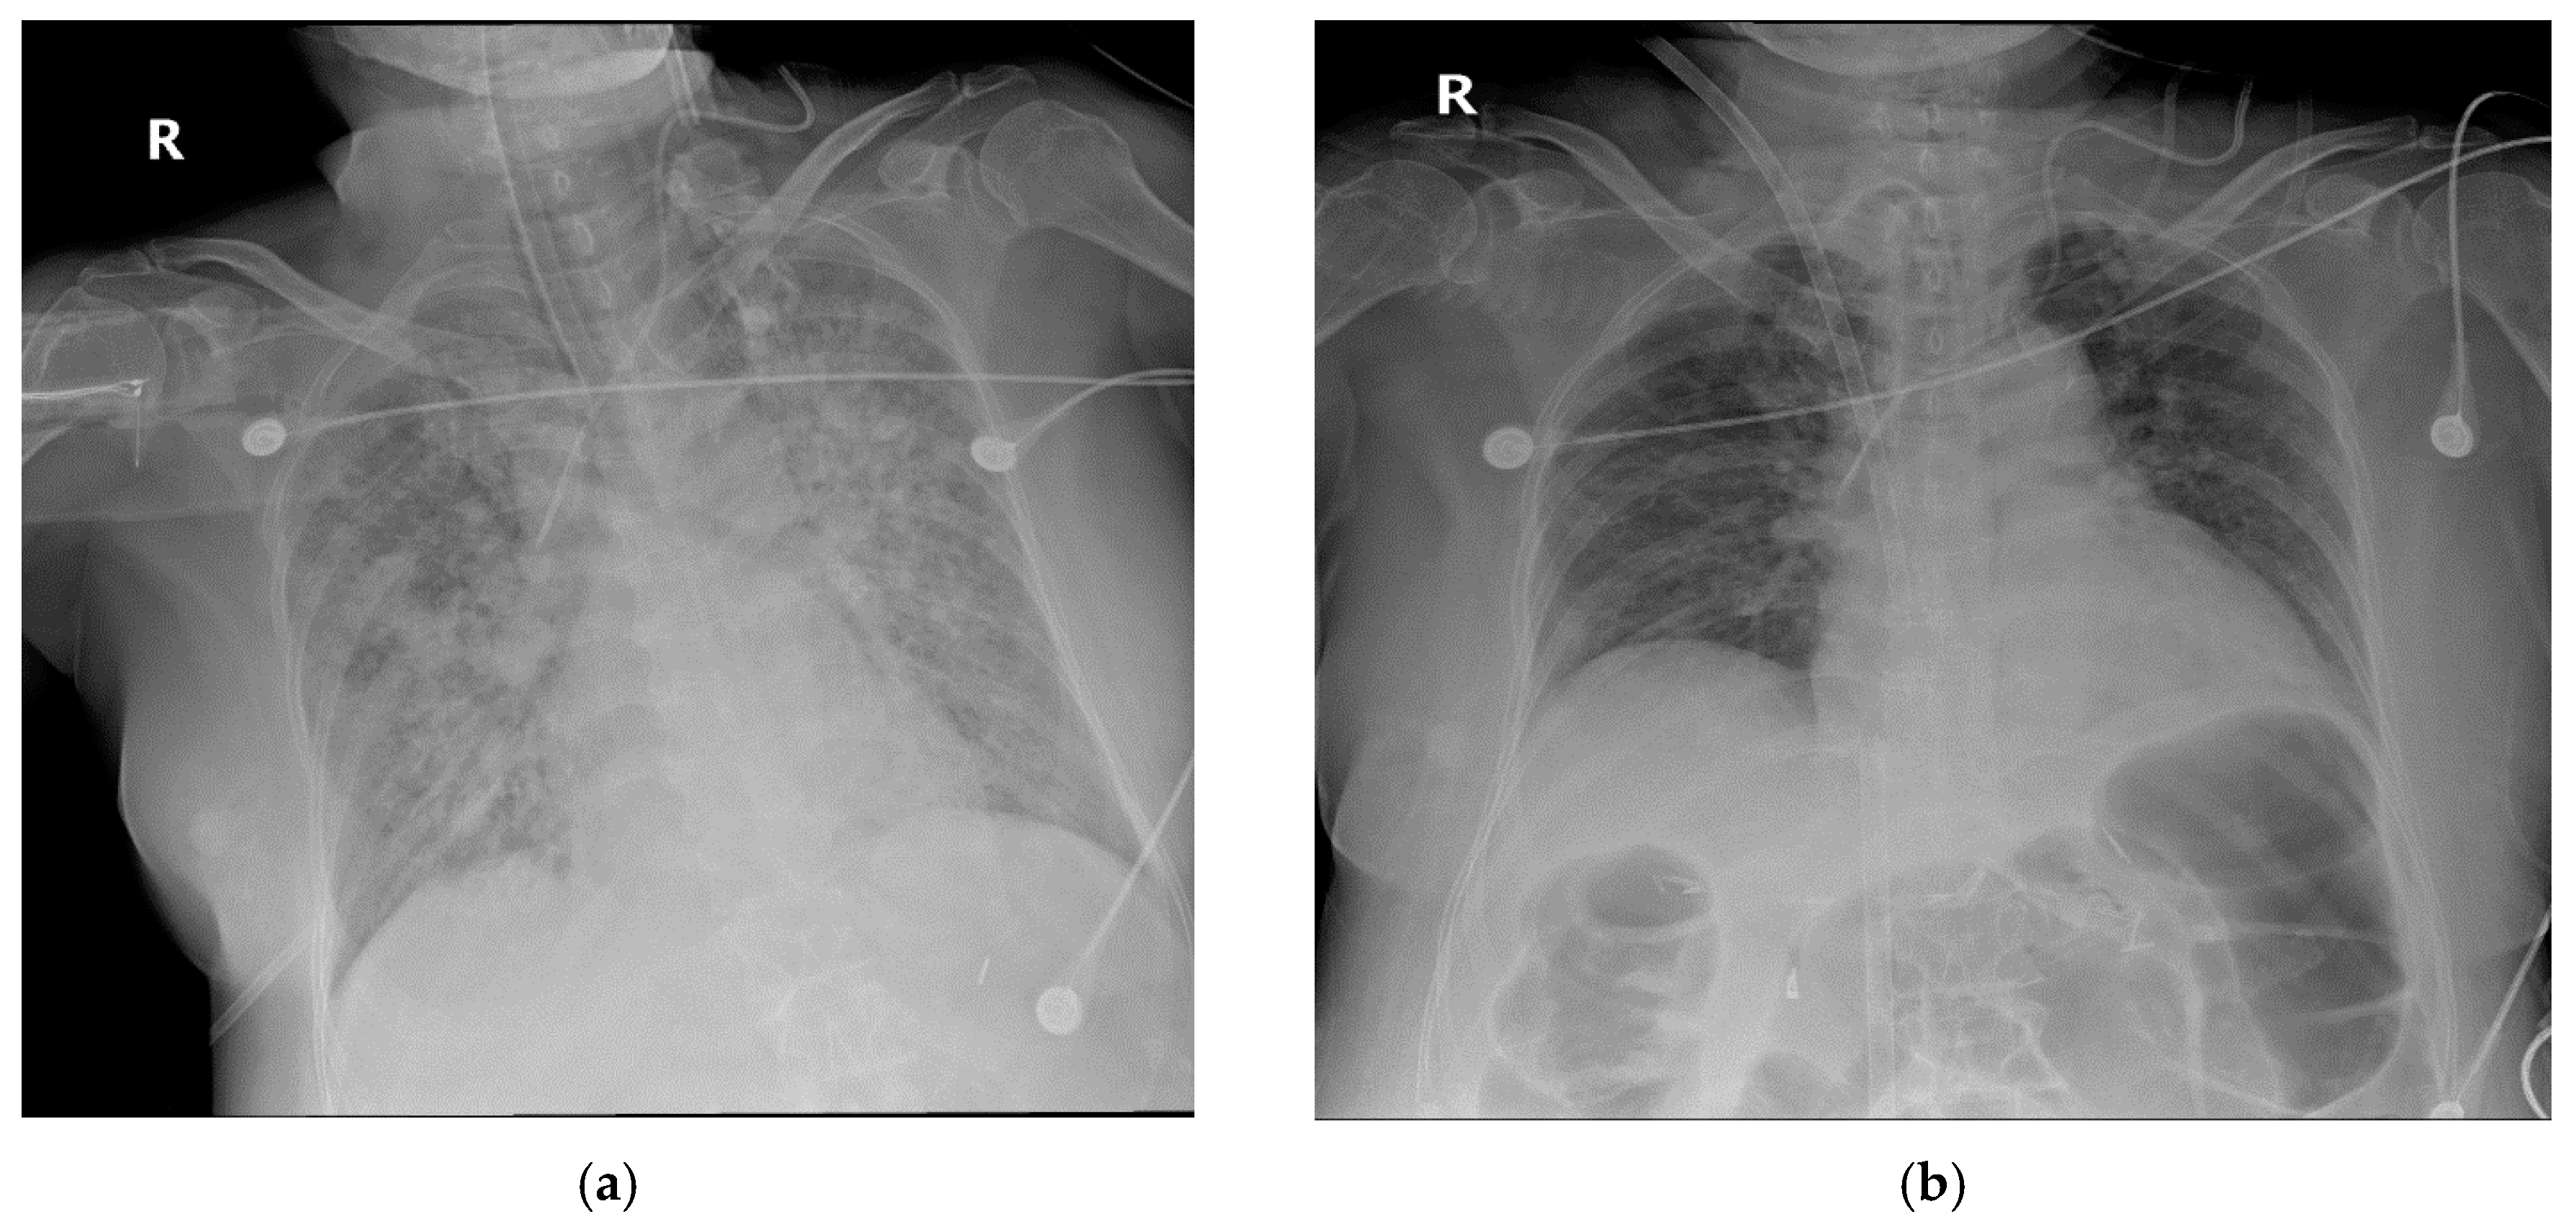

2.2. Case 2

2.3. Case 3